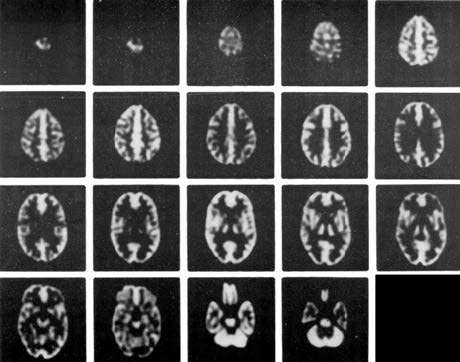

-在腦部SPECT及腦部PET的研究中,從解刨學角度精確的模擬放射性分布;在MRI研究中,精確模擬質(zhì)子密度及馳豫參數(shù)打的分布

Anatomically accurate simulation of radioactivity distribution for brain SPECT and brain PET studies* and distribution of proton density and relaxation parameters for brain MRI studies

-在血流和代謝研究中模擬正?;屹|(zhì)和白質(zhì)的4:1攝取率(按部分體積效應模擬)

Simulates 4:1 uptake ratio (by partial volume effect) seen for normal gray and white matter in flow and metabolic studies

-單體填充腔設計,消除了制備不同濃度放射性物質(zhì)的必要

Single fillable chamber eliminates the necessity of preparing different concentrations of radioactivity

-為基底神經(jīng)節(jié)區(qū)域提供了可填充固體缺陷

Fillable and solid defects for basil ganglia region available